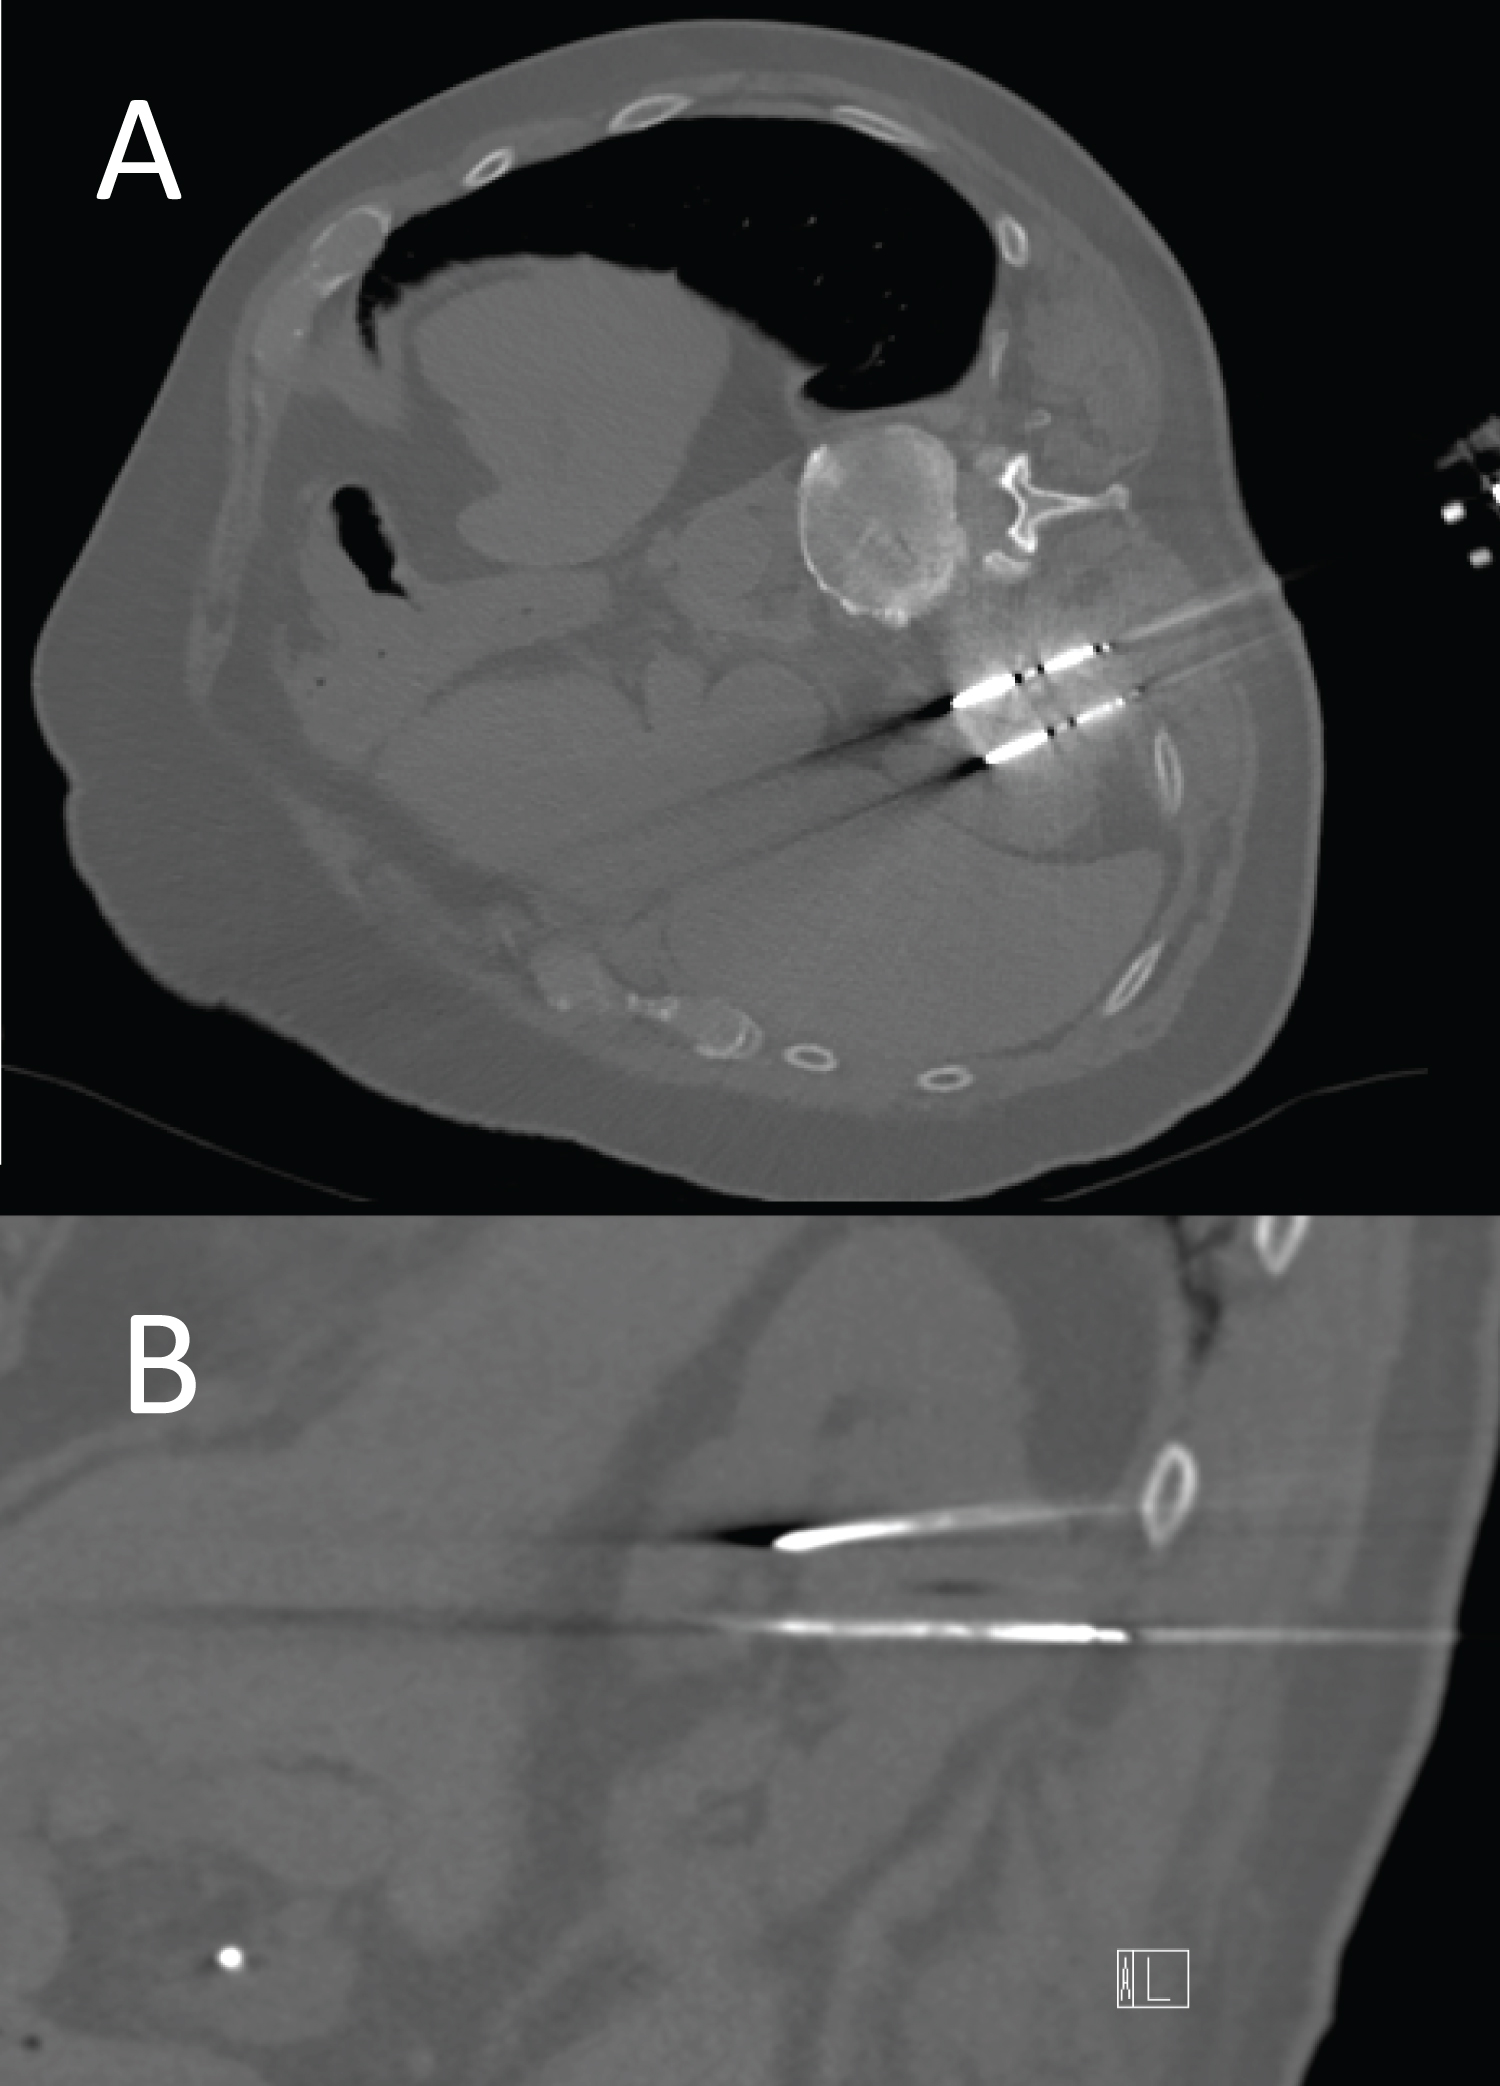

Figure 2: Axial (A) and sagittal (B) images from the ablation show 3 probes within the mass. Anterior aspects of the tips enter into the renal collecting system. The upper probe is seen to take a transpleural course. The expected ablation zone was 4 cm wide by 5.3 cm long. Repeat biopsy at the time of ablation confirmed prior diagnosis of oncocytoma. View Figure 2